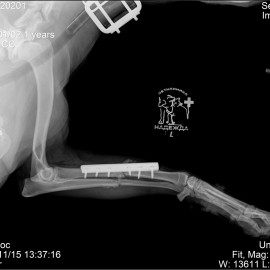

Рентгенологические снимки до операции.

Жалобы на хромоту на переднюю лапу в течение 3-х недель после перенесенной травмы. После проведенных исследований собаке был поставлен диагноз - застарелый перелом костей левого предплечья. Кости стали срастаться неправильно. Проведена операция - корригирующий остеосинтез костей левого предплечья.